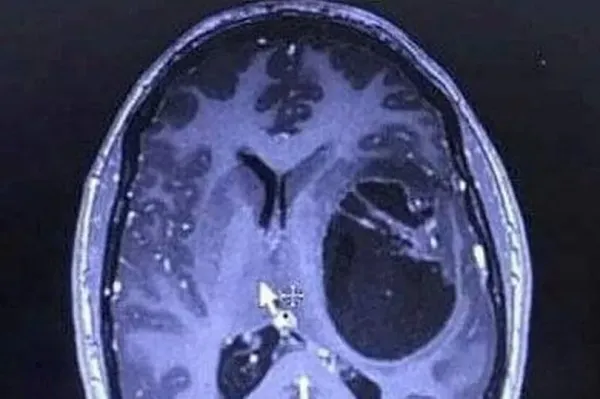

A mum who blamed her headaches and nausea on side effects from new fibromyalgia tablets was told she had stage four brain cancer after collapsing at her workplace. Verity Phillips received a glioblastoma diagnosis in February 2022 and was told she had just 12 to 18 months left.

Following her collapse at work, she thought her symptoms stemmed from her new medication she'd been using - but her health worsened and she was rushed to hospital. Soon, scans revealed a growth on her brain, leading to the 35-year-old being transferred to Hull Royal Infirmary where surgeons drained surplus fluid and performed a biopsy that subsequently confirmed her brain cancer diagnosis.

"When the doctors showed us the scan and said there was a mass on my brain, we were devastated. Doctors told me that without treatment I could have just months to live – with treatment, maybe 12 to 18 months."